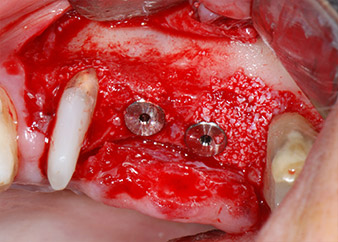

listos para los tornillos de cubierta

Fig. 12: Los dos implantes están colocados y listos para los tornillos de cubierta.